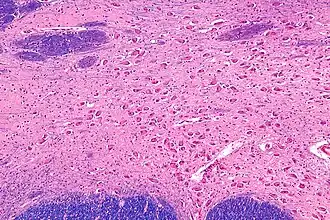

Intermediate magnification micrograph of the nucleus basalis. LFB-HE stain.